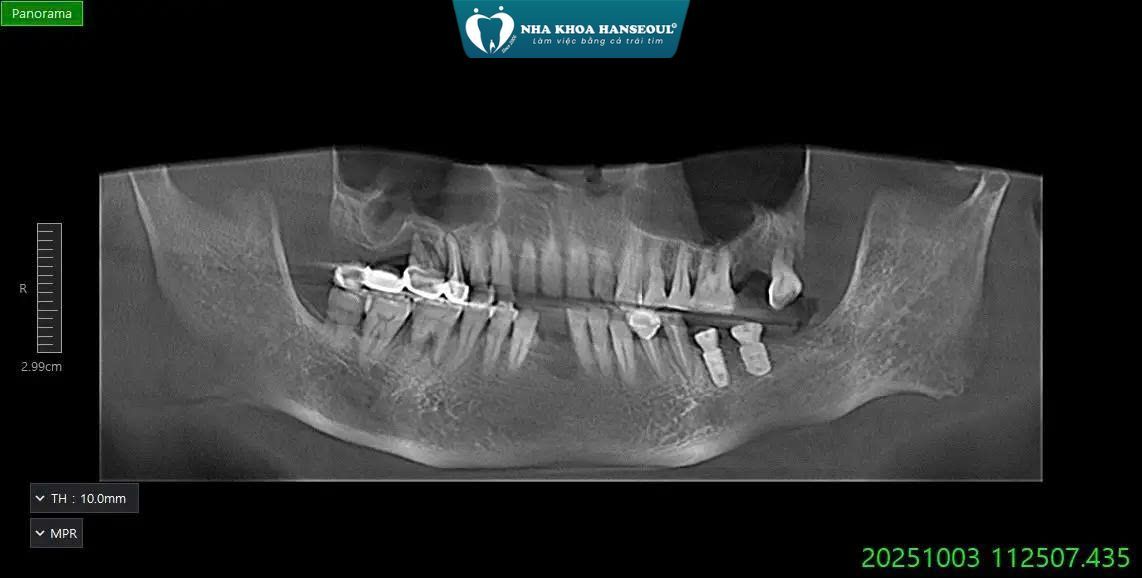

2.2 Cấy 2 trụ Implant Osstem SA tại vị trí R36 – R37

2.3 Phục hình 2 răng sứ trên Implant

2.4 Gắn Healing (trụ lành thương)

Sau khi đặt trụ, bác sĩ tiến hành:

- Gắn trụ Healing giúp định hình nướu

- Tạo viền nướu thẩm mỹ để sẵn sàng cho bước lấy dấu và gắn răng phục hình sau này

3 KẾT QUẢ SAU ĐIỀU TRỊ

Sau quy trình điều trị chuẩn y khoa, anh Dũng ghi nhận những thay đổi tích cực:

- Giảm đau rõ rệt sau nhổ răng và làm sạch viêm

- Trụ Implant tích hợp tốt – nướu lành đẹp nhờ gắn Healing chuẩn

- Khả năng ăn nhai phục hồi mạnh mẽ sau khi gắn răng Titanium

- Thẩm mỹ vùng hàm dưới cải thiện rõ rệt

- Không còn viêm, sưng kéo dài như trước